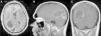

El xantoastrocitoma pleomórfico (XAP) es un tumor astrocitario raro, de localización más frecuente superficial en hemisferios cerebrales de niños y adultos jóvenes. Se trata de un tumor de bajo grado que tiene un pronóstico relativamente favorable; sin embargo, se han descrito pacientes con progresión maligna. Presentamos así un caso inusual de un varón de 54 años con una tumoración multiquística parietooccipital derecha con extensión intraventricular. Tras la exéresis quirúrgica el estudio histológico mostró una lesión con células pleomórficas, cúmulos de lípidos en su citoplasma, cuerpos granulares intensamente eosinófilos, núcleos únicos bien delimitados y positividad inmunohistoquímica frente a sinaptofisina, proteína gliofibrilar ácida (GFAP), proteína S-100, vimentina y CD56 de forma focal. Tras descartar otras entidades, como metástasis por carcinoma de células grandes y una lesión primaria tipo astrocitoma subependimario de células grandes, se diagosticó de XAP. A los 9 meses de seguimiento el paciente presentó una extensa recidiva tumoral local considerada irresecable, con deterioro neurológico progresivo y signos radiológicos de progresión maligna, confirmados histológicamente mediante la realización de una biopsia cerebral que demostró cambios respecto a la lesión inicial que incluían focos de necrosis, mayor actividad mitótica (5×10 campos de gran aumento) e índice de proliferación celular medido con la tinción nuclear de Ki67 del 10%. El presente caso ilustra la extensión intraventricular, así como un comportamiento agresivo no característico de estas lesiones (similar a un astrocitoma anaplásico o glioblastoma primario), exigiendo un tratamiento quirúrgico óptimo inicial con seguimiento estrecho clínico-radiológico, considerando el potencial de transformación maligna del XAP.

Pleomorphic xanthoastrocytoma (PXA) is a rare, low-grade astrocytic tumour that usually occurs in the superficial cerebral hemispheres of children and young adults. Although it has a relatively favourable prognosis, malignant progression of these tumours has been described. Therefore, we present an unusual case of a 54-year-old male with a right, multicystic, parietooccipital tumour extending through the ipsilateral ventricle. After surgical resection, histological examination revealed a lesion with pleomorphic cells, cytoplasmic lipidisation, intensely eosinophilic granular bodies, well-delimitated unique nuclei and focal, positive immunoreactivity for synaptophysin, glial fibrillary acidic protein (GFAP), S-100 protein, vimentin and CD56. Once other tumours, such as giant cell metastatic carcinoma or primary lesion like subependymal giant cell astrocytoma, were ruled out, a final diagnosis of XAP was established. After a follow-up period of 9 months, the patient suffered an extensive and local tumour relapse considered inoperable, with progressive neurological deterioration and radiological findings of malignant progression. The brain biopsy procedure revealed anaplastic changes, including necrosis foci, higher mitotic activity (5×10 high-power fields) and a 10% proliferation index measured by Ki67 labelling. The present case showed intraventricular extension and a more aggressive behaviour, both uncommon in these tumours (similar to anaplastic astrocytoma or glioblastoma multiforme), thus demanding an initial, optimal surgical treatment with close clinical and radiological follow-up, due to the high potential for malignant transformation of XAPs.